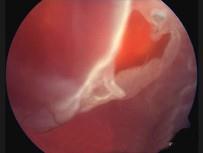

孔源性视网膜脱离(如图)的易患因素有 ( )A、眼外伤B、以上都是C、视网膜格子样变性D、高度近视E、无晶状体眼

问题 孔源性视网膜脱离(如图)的易患因素有 ( )

选项 A、眼外伤 B、以上都是 C、视网膜格子样变性 D、高度近视 E、无晶状体眼

答案 B